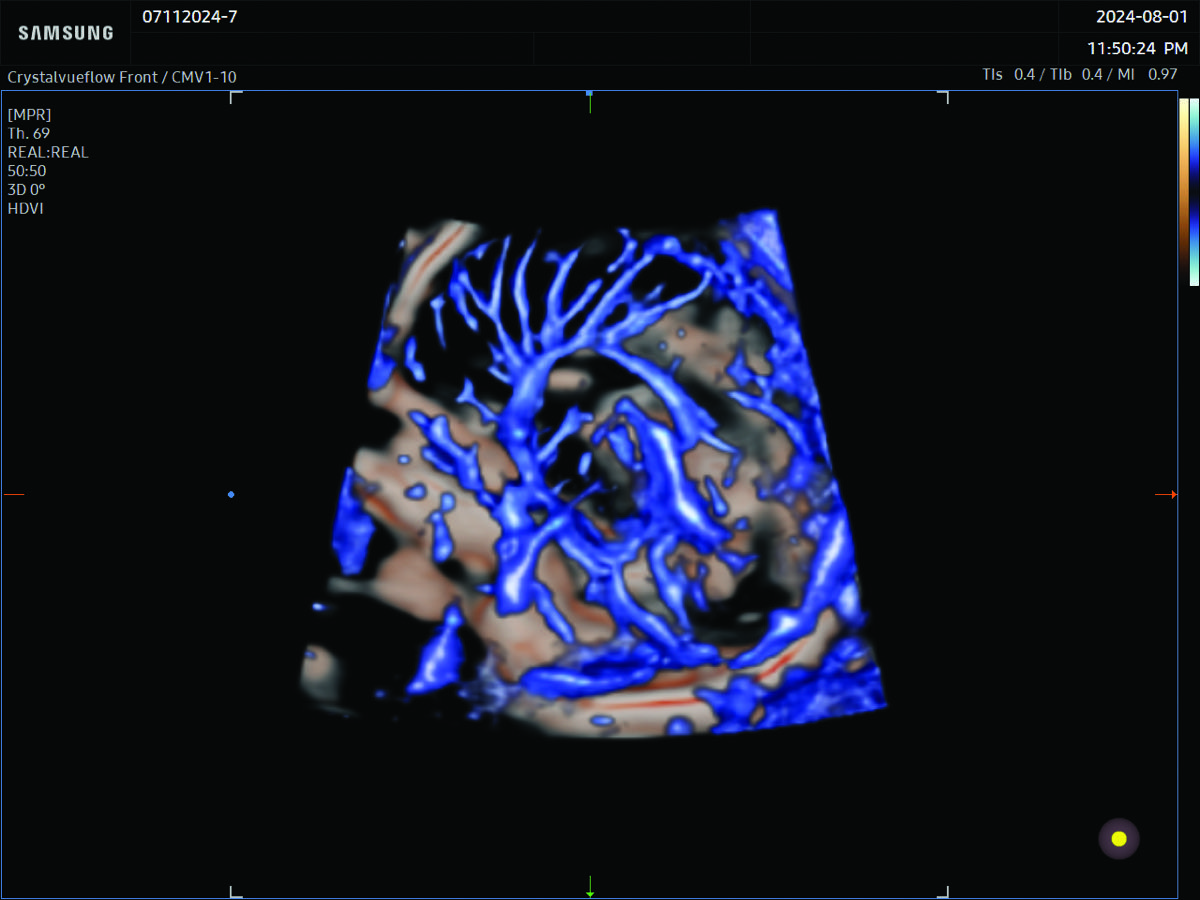

Comprehensive, advanced and expert MFM care for high-risk pregnancies

- Fetal anomalies